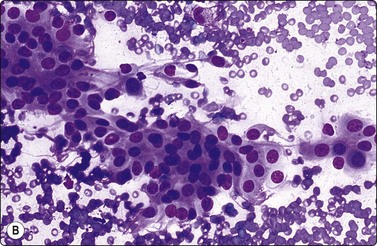

Large cell carcinoma (Figs 8.31 and 8.32)

Usual findings

Large, highly pleomorphic cells with abundant cytoplasm,

Large multilayered fragments of malignant tissue,

Dispersed cells with a high N:C ratio,

Tumor giant cells,

Polymorph ingestion,

Fragile cytoplasm.

image

Fig. 8.31 Giant cell carcinoma

Pure population of multinucleate malignant cells (MGG, HP).

image image

Fig. 8.32 Giant cell carcinoma

(A) Giant tumor cell with prominent neutrophil ingestion; (B) Positive immunostaining for AE1/AE3 keratins (A, H&E, HP; B, IPOX, HP).

Large cell carcinoma is a diagnosis of exclusion in that cytological features of squamous, glandular or neuroendocrine differentiation are absent in a non-small cell carcinoma.88 It may be necessary to examine large areas histologically to ensure that differentiation is lacking. This diagnosis can therefore never be established by FNAC alone. Instead, we use the category of poorly differentiated large cell or non-small cell carcinoma to designate non-small cell tumors in which further subtyping is not possible. Many of these prove to be squamous cell carcinoma or adenocarcinoma after histological examination, and the category is virtually eliminated if typing by electron microscopy is used. As previously discussed, attempts should be made to further classify ‘non-small cell’ carcinoma in cytological specimens using immunohistochemistry. Tumors showing dual differentiation such as adenosquamous carcinoma are uncommonly diagnosed cytologically.231 Carcinosarcoma (see Fig. 8.54),240 sarcomatoid/spindle cell carcinoma241 or blastoma242 are other considerations in poorly differentiated tumors with a spindle component.

The findings in large cell carcinoma are highly variable; those listed are the common features but have little specific diagnostic value, and other cytological patterns may occur. For example, in those tumors diagnosed as large cell carcinoma by subsequent histology, there is often a high N:C ratio and cell dispersal may be striking. An appearance resembling melanoma may sometimes be observed. Polymorph ingestion appears to be linked to an abundance of cytoplasm and cell pleomorphism rather than any particular form of differentiation, and virtually any tumor may demonstrate this phenomenon. FNAC findings in lymphoepithelioma-like carcinomas have been described.243

Pure giant cell carcinomas have been diagnosed cytologically (Figs. 8.31 and 8.32), although immunostaining is necessary to confirm carcinoma.244 They are said to be peripheral highly aggressive neoplasms, but occasionally, smaller resectable tumors are encountered.245